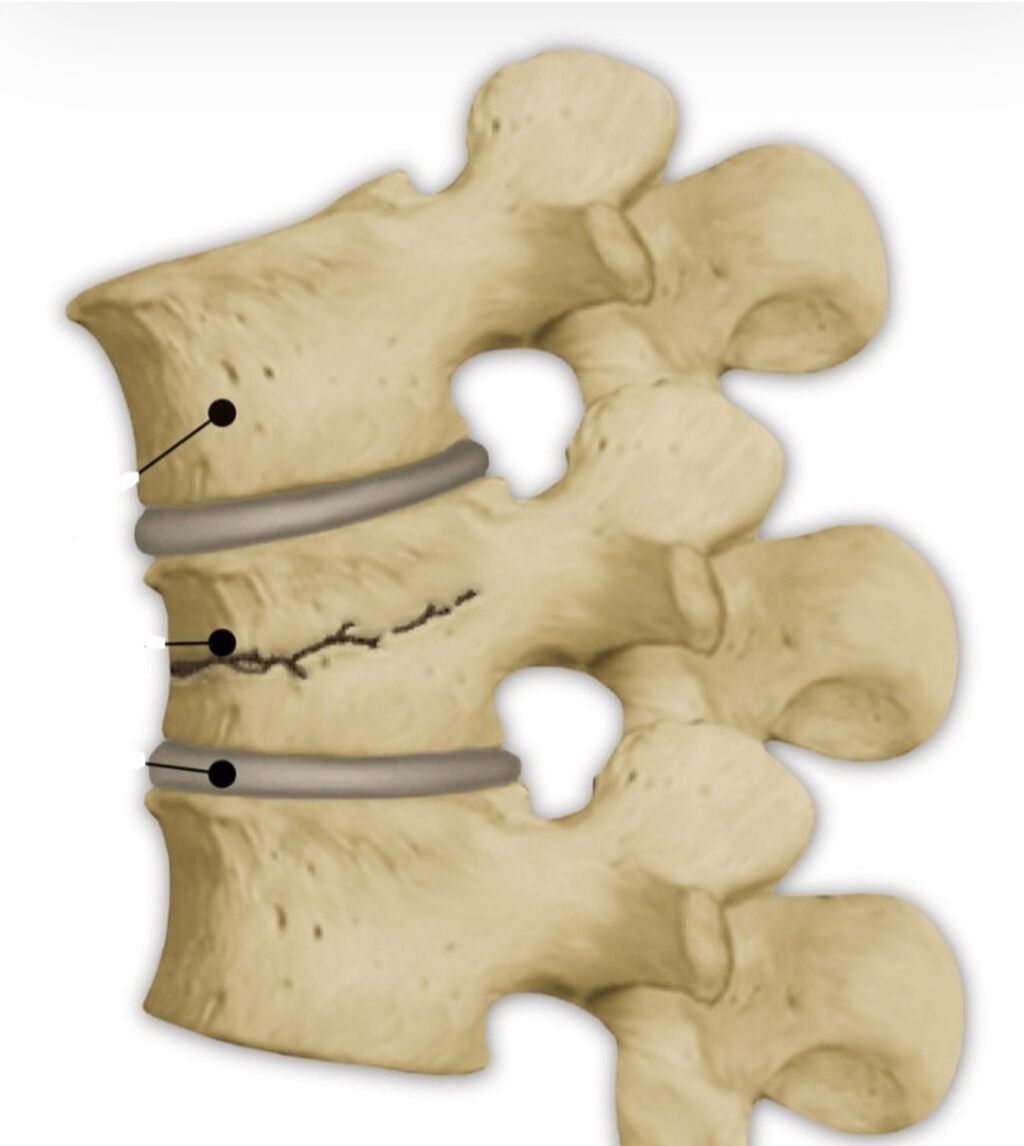

Рентгеновские снимки и медицинские изображения компрессионных переломов